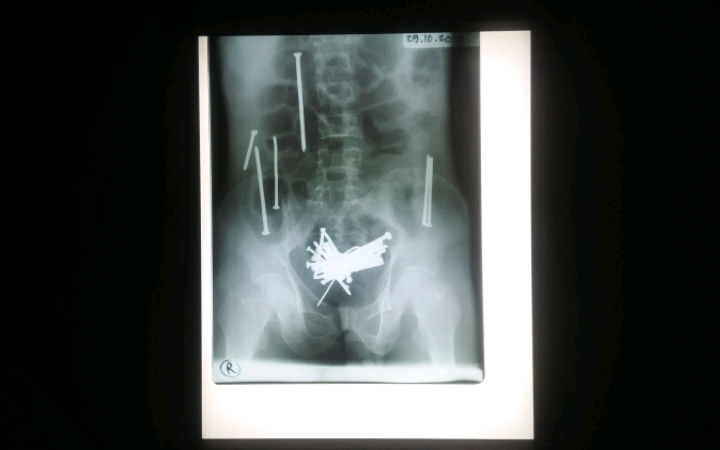

JABAR NEWS | KOTA TASIKMALAYA – Wawan (42) si pemakan paku dari Tasikmalaya saat ini tengah menjalani proses perawatan medis di ruang ICU RS dr Soekardjo usai operasi, Rabu (01/11/2017).

Tim Medis RS dr Soekarjo yakni dokter ahli bedah berhasil mengeluarkan 48 paku berkarat berbagai ukuran dari usus besar dan kecilnya.

Menurut keterangan Dokter Spesialis Bedah RS dr Soekardjo Yarie Hermawan operasi pengambilan paku di tubuh Wawan cukup rumit bagi tim dokter. Yang pertama dilihat dari segi panjangnya bervariasi, lokasi paku juga tersebar dimulai dari usus besar bawah, usus besar atas serta usus halus hingga sulit diangkat.

Selaku Tim ahli bedah mereka juga harus menyayat empat titik dalam usus Wawan guna mengeluarkan paku. Dan 48 paku berbagai ukuran yang sudah berkarat berhasil dikeluarkan.

Yarie juga mengungkapkan beberapa fakta lain. Selain paku, tim dokter ahli bedah juga menemukan gumpalan rambut dalam usus besar.

“Selain 48 paku kita juga menemukan rambut tapi tidak banyak, terpisah sendiri di bagian usus besar,” ucapnya.